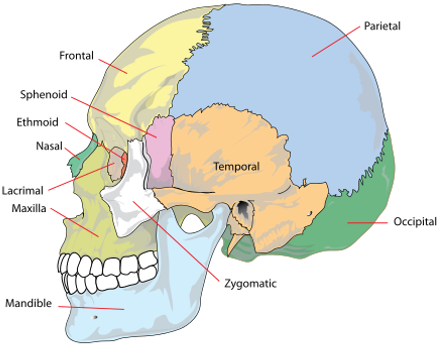

Identify the 8 cranial bones of the skull.

Cranial Stutures & Junctions

The frontal and parietal bones? Coronal

The parietal and occipital bones? Lambdoid

Between parietal bones? Sagittal

Nasion (joins the nasal part of the frontal bone and the nasal bone)

Pterion (joins frontal, parietal, temporal and sphenoid bones)

Bregma (joins frontal and parietal bones)

Lambda (joins occipital and parietal bones)